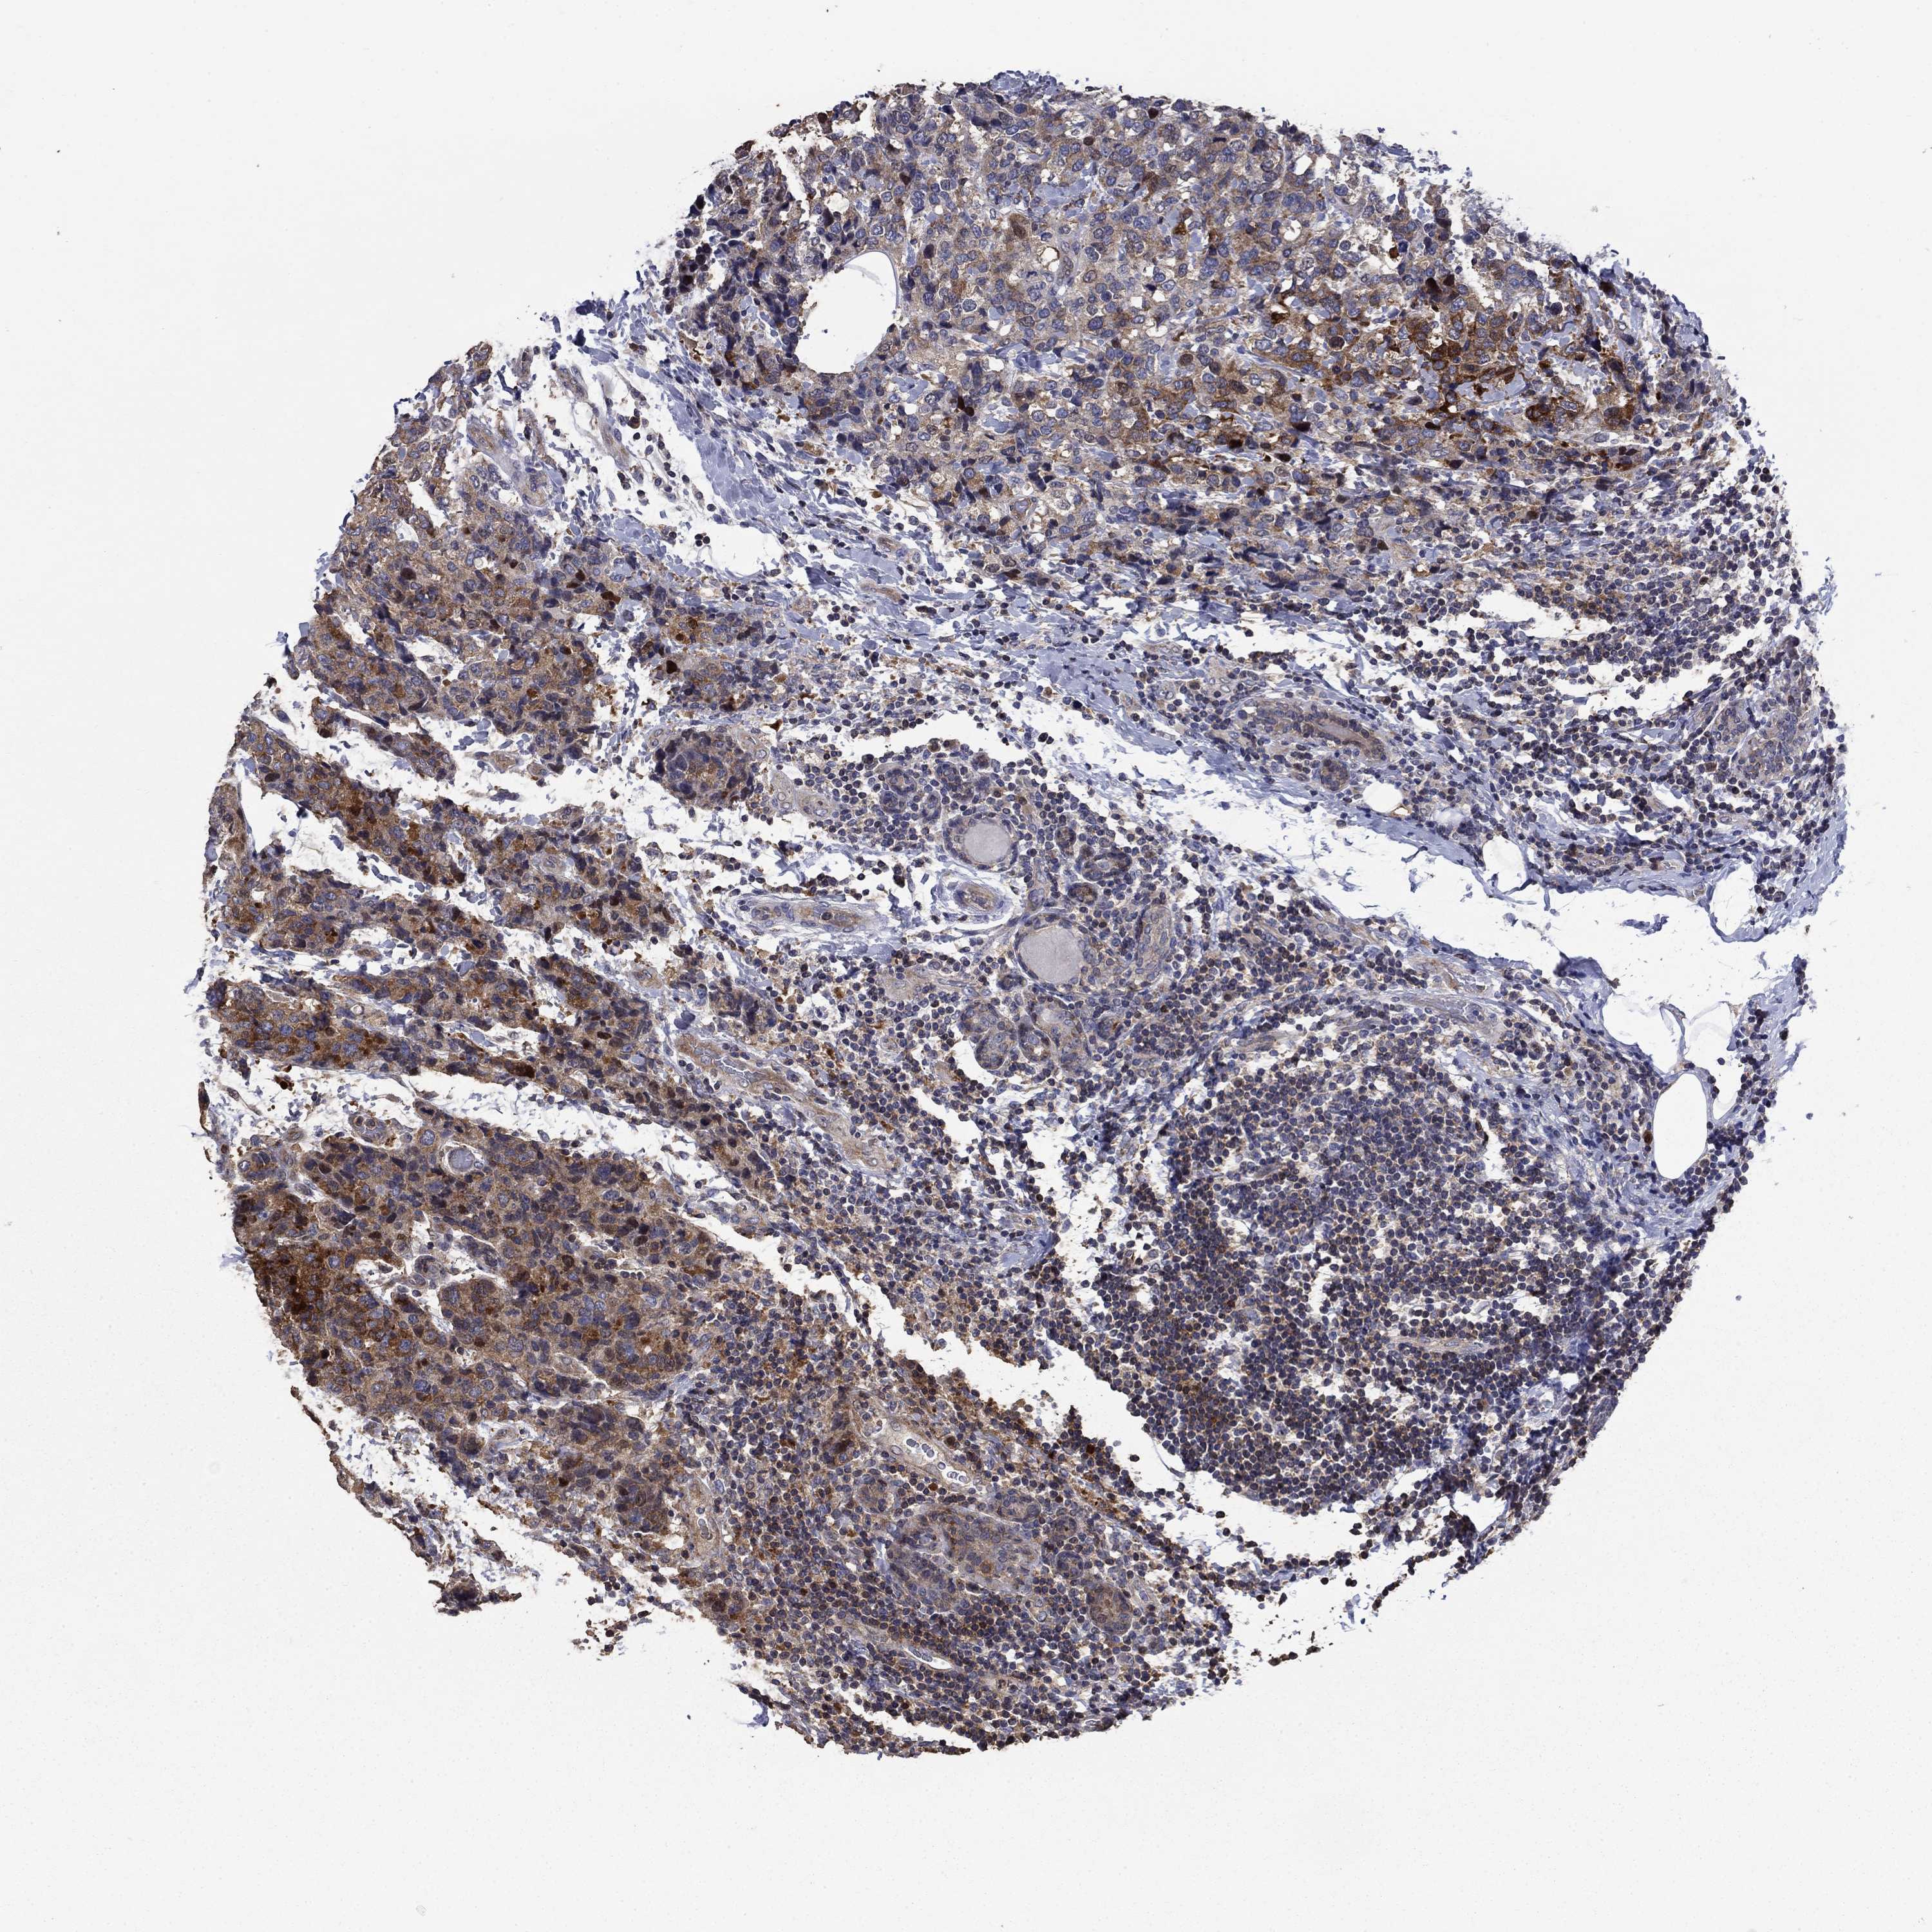

CANCER BREAST CANCER Show tissue menu

BRCA TCGA BRCA VALIDATION PROTEIN EXPRESSION